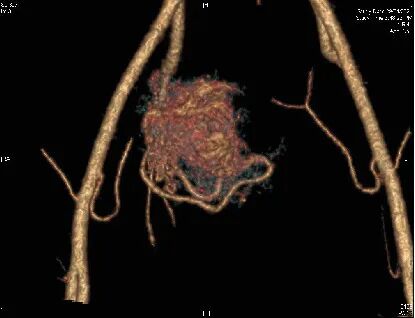

为了看清这团血管的真面目和它的势力范围,医生安排她做了CT血管造影。

这个检查就像给子宫的血管系统拍了一张高清三维地图,放射科的医生看了之后,确认了这是子宫动静脉畸形。

当然,增强CT或核磁共振血管成像能清晰显示畸形血管团的位置、大小、范围以及它和周围血管的关系,对于制定治疗方案至关重要。